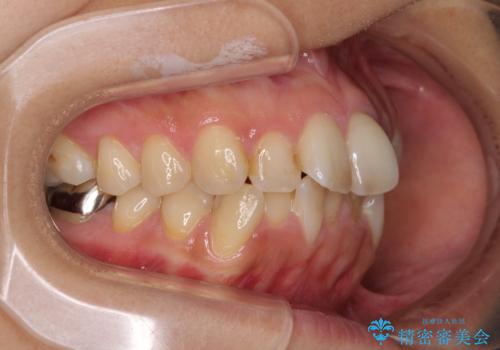

デコボコと口元の突出感 ハーフリンガルでの抜歯矯正

- 前歯のデコボコと上顎の前突感による口の閉じにくさを気にして来院された患者様です。

目立たない装置を希望されたので、上顎が裏側装置のハーフリンガルを選択し、上下左右の小臼歯(計4歯)を抜歯して矯正治療を行うこととしました。

表側のワイヤー矯正に比べると治療期間は長く、費用も高額となりますが、どうしても目立たせたくないという方にはお勧めの抜歯矯正です。